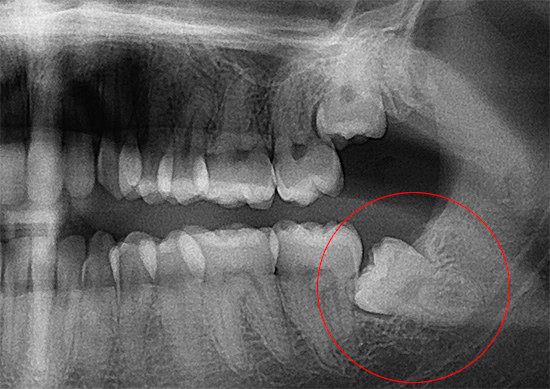

- o grande volume e a invasão da próxima intervenção cirúrgica (por exemplo, através de raios-x, às vezes você pode antecipar a remoção complexa de dentes do siso com antecedência);

- A capacidade de realizar operações longas e complexas para remover um ou mais dentes, especialmente nos casos em que os dentes têm uma estrutura complexa e uma posição incorreta na mandíbula. Isto é especialmente verdade. ao remover os dentes inferiores da sabedoria, uma vez que a estrutura e a localização desses dentes na mandíbula são absolutamente imprevisíveis.

“Ontem, o dente do siso inferior foi removido sob anestesia geral. A operação durou aproximadamente 40 minutos, como fui informado. Os médicos disseram que na foto meu dente estava enraizado no próximo, então eu tive que cortá-lo por um longo tempo e retirá-lo em pedaços. Eu certamente não teria sobrevivido a esse espetáculo em minha mente, e eles me fizeram dormir bem, então não ouvi ou vi nada. O único ponto negativo é o desagradável catador de anestesia, e havia uma boca seca e terrível, pois após uma ressaca severa, minha cabeça estava zumbindo por algumas horas, mas está tudo para trás. Estou satisfeito que tudo correu bem. "